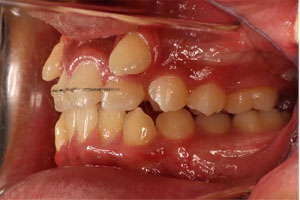

こちらの初診(男性)の患者さんは、開咬合 / 叢生歯列の症状がありました。

1期治療 8歳9ヶ月 2期治療 12歳4ヶ月から治療を開始し、1期治療 7ヶ月 2期治療 2年5ヶ月の間、スタンダードエッジワイズ法(与五沢エッジワイズシステム)を用い矯正治療を行いました。

| 症例分類 | 開咬合 / 叢生歯列 / 偏位咬合 | |||||||||||||||||||||||||||||||||||||||||||||||||||||||||||